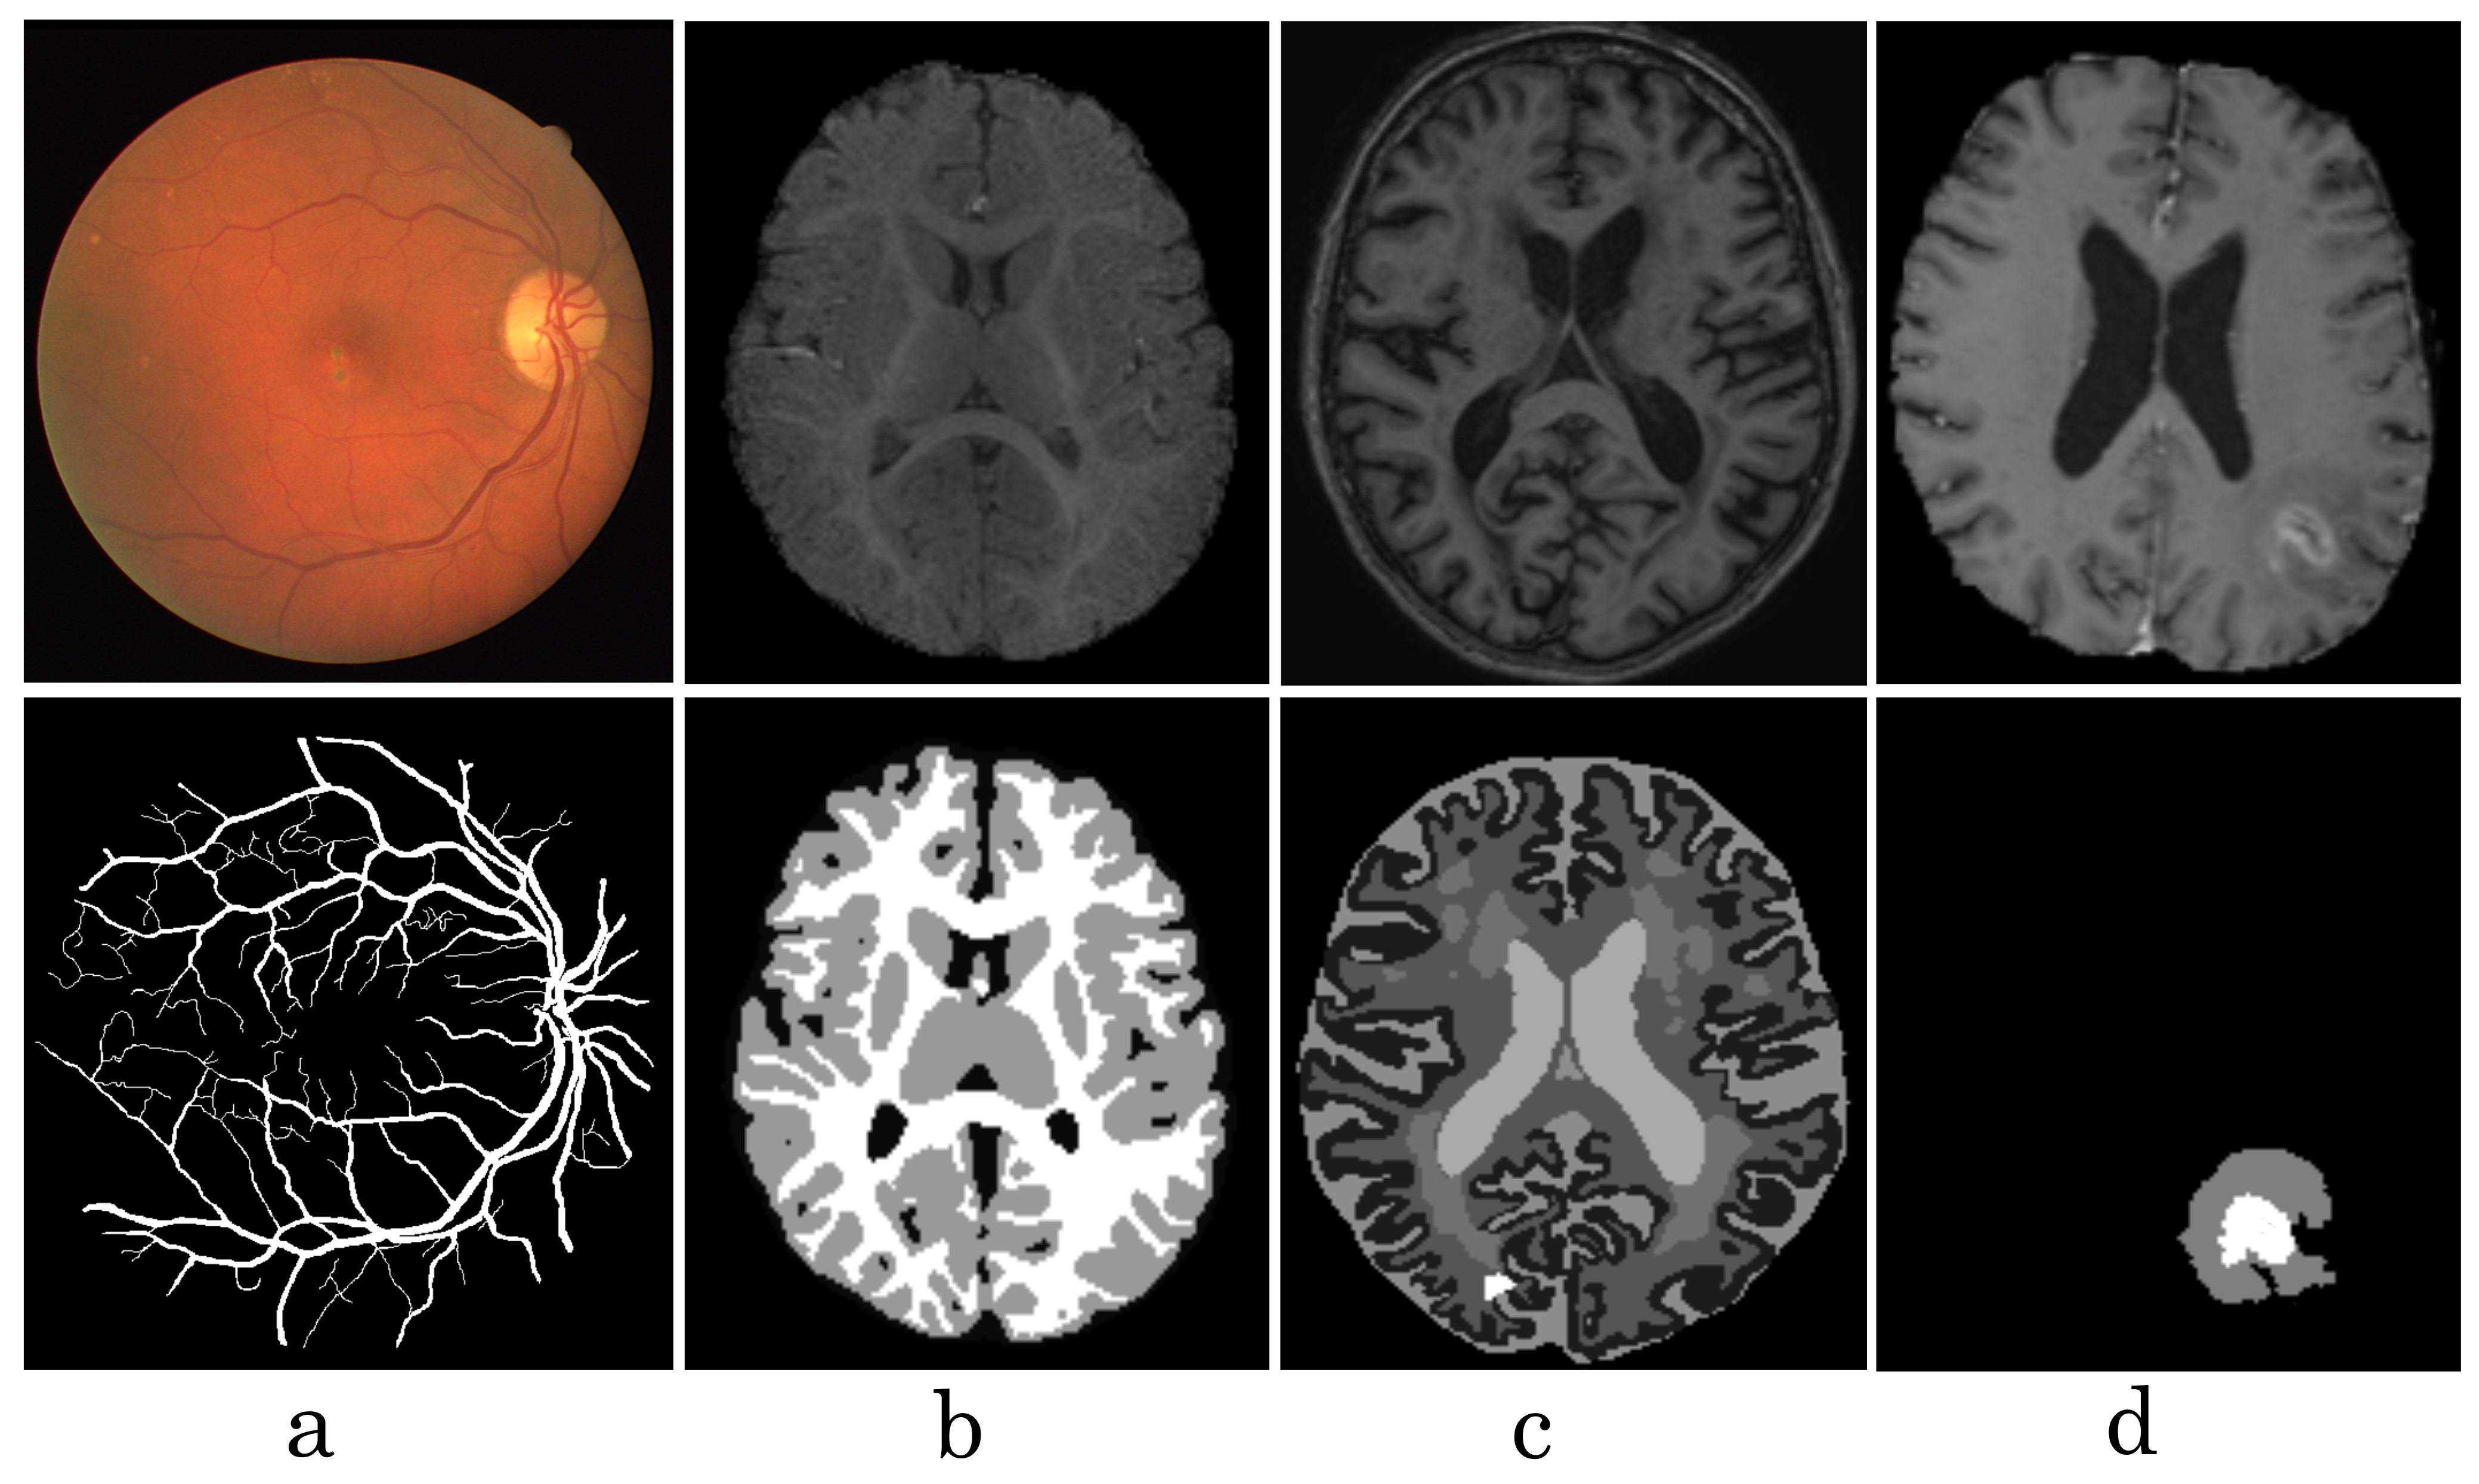

Figure 1.

Visualization of some medical images from different datasets, such as DRIVE (a), iSeg17 (b), MRBrainS18 (c), Brats18 (d). The first row shows raw input images, the second row shows labeled images.